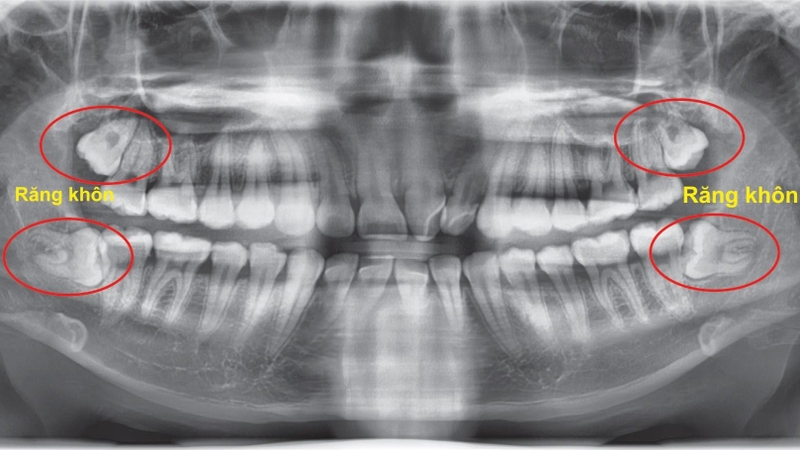

• Kiểm tra sự phát triển của răng khôn: Nó cũng hữu ích trong việc theo dõi sự phát triển của răng khôn và xác định các răng mọc ngầm trong hàm của trẻ.

• Hỗ trợ trong chỉnh nha: Bác sĩ có thể sử dụng hình ảnh X-quang để có cái nhìn tổng thể về xương hàm và răng của trẻ trước khi quyết định liệu trình chỉnh nha phù hợp.

Chụp panorama răng 2

Bác sĩ có thể sử dụng hình ảnh X-quang để đánh giá tình trạng răng khôn

• Hỗ trợ trong quyết định can thiệp nha khoa: Bác sĩ có thể sử dụng hình ảnh X-quang để đánh giá tình trạng răng trước khi quyết định tiến hành các thủ thuật như niềng răng, nhổ răng khôn, trồng răng implant hoặc các can thiệp nha khoa khác.